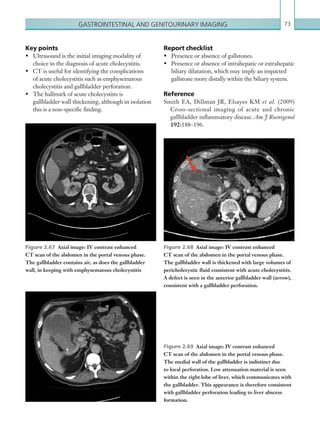

Figures 1.20a, b  Axial images: IV contrast enhanced CT scans of the thorax. There is a combination of

interlobular septal thickening and patchy ground glass opacity, resulting in a crazy paving appearance.

Figure 1.21  AP chest radiograph. There are bilateral,

perihilar airspace opacities consistent with alveolar

oedema. The costophrenic angles are not visible due to

bilateral pleural effusions.

Figure 1.22  Axial image: IV contrast enhanced

CT scan of the thorax in the arterial phase. There is

subendocardial fat deposition at the LV apex in keeping

with previous myocardial infarction.